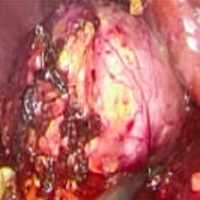

Renal myxoma: An unforeseen diagnosis